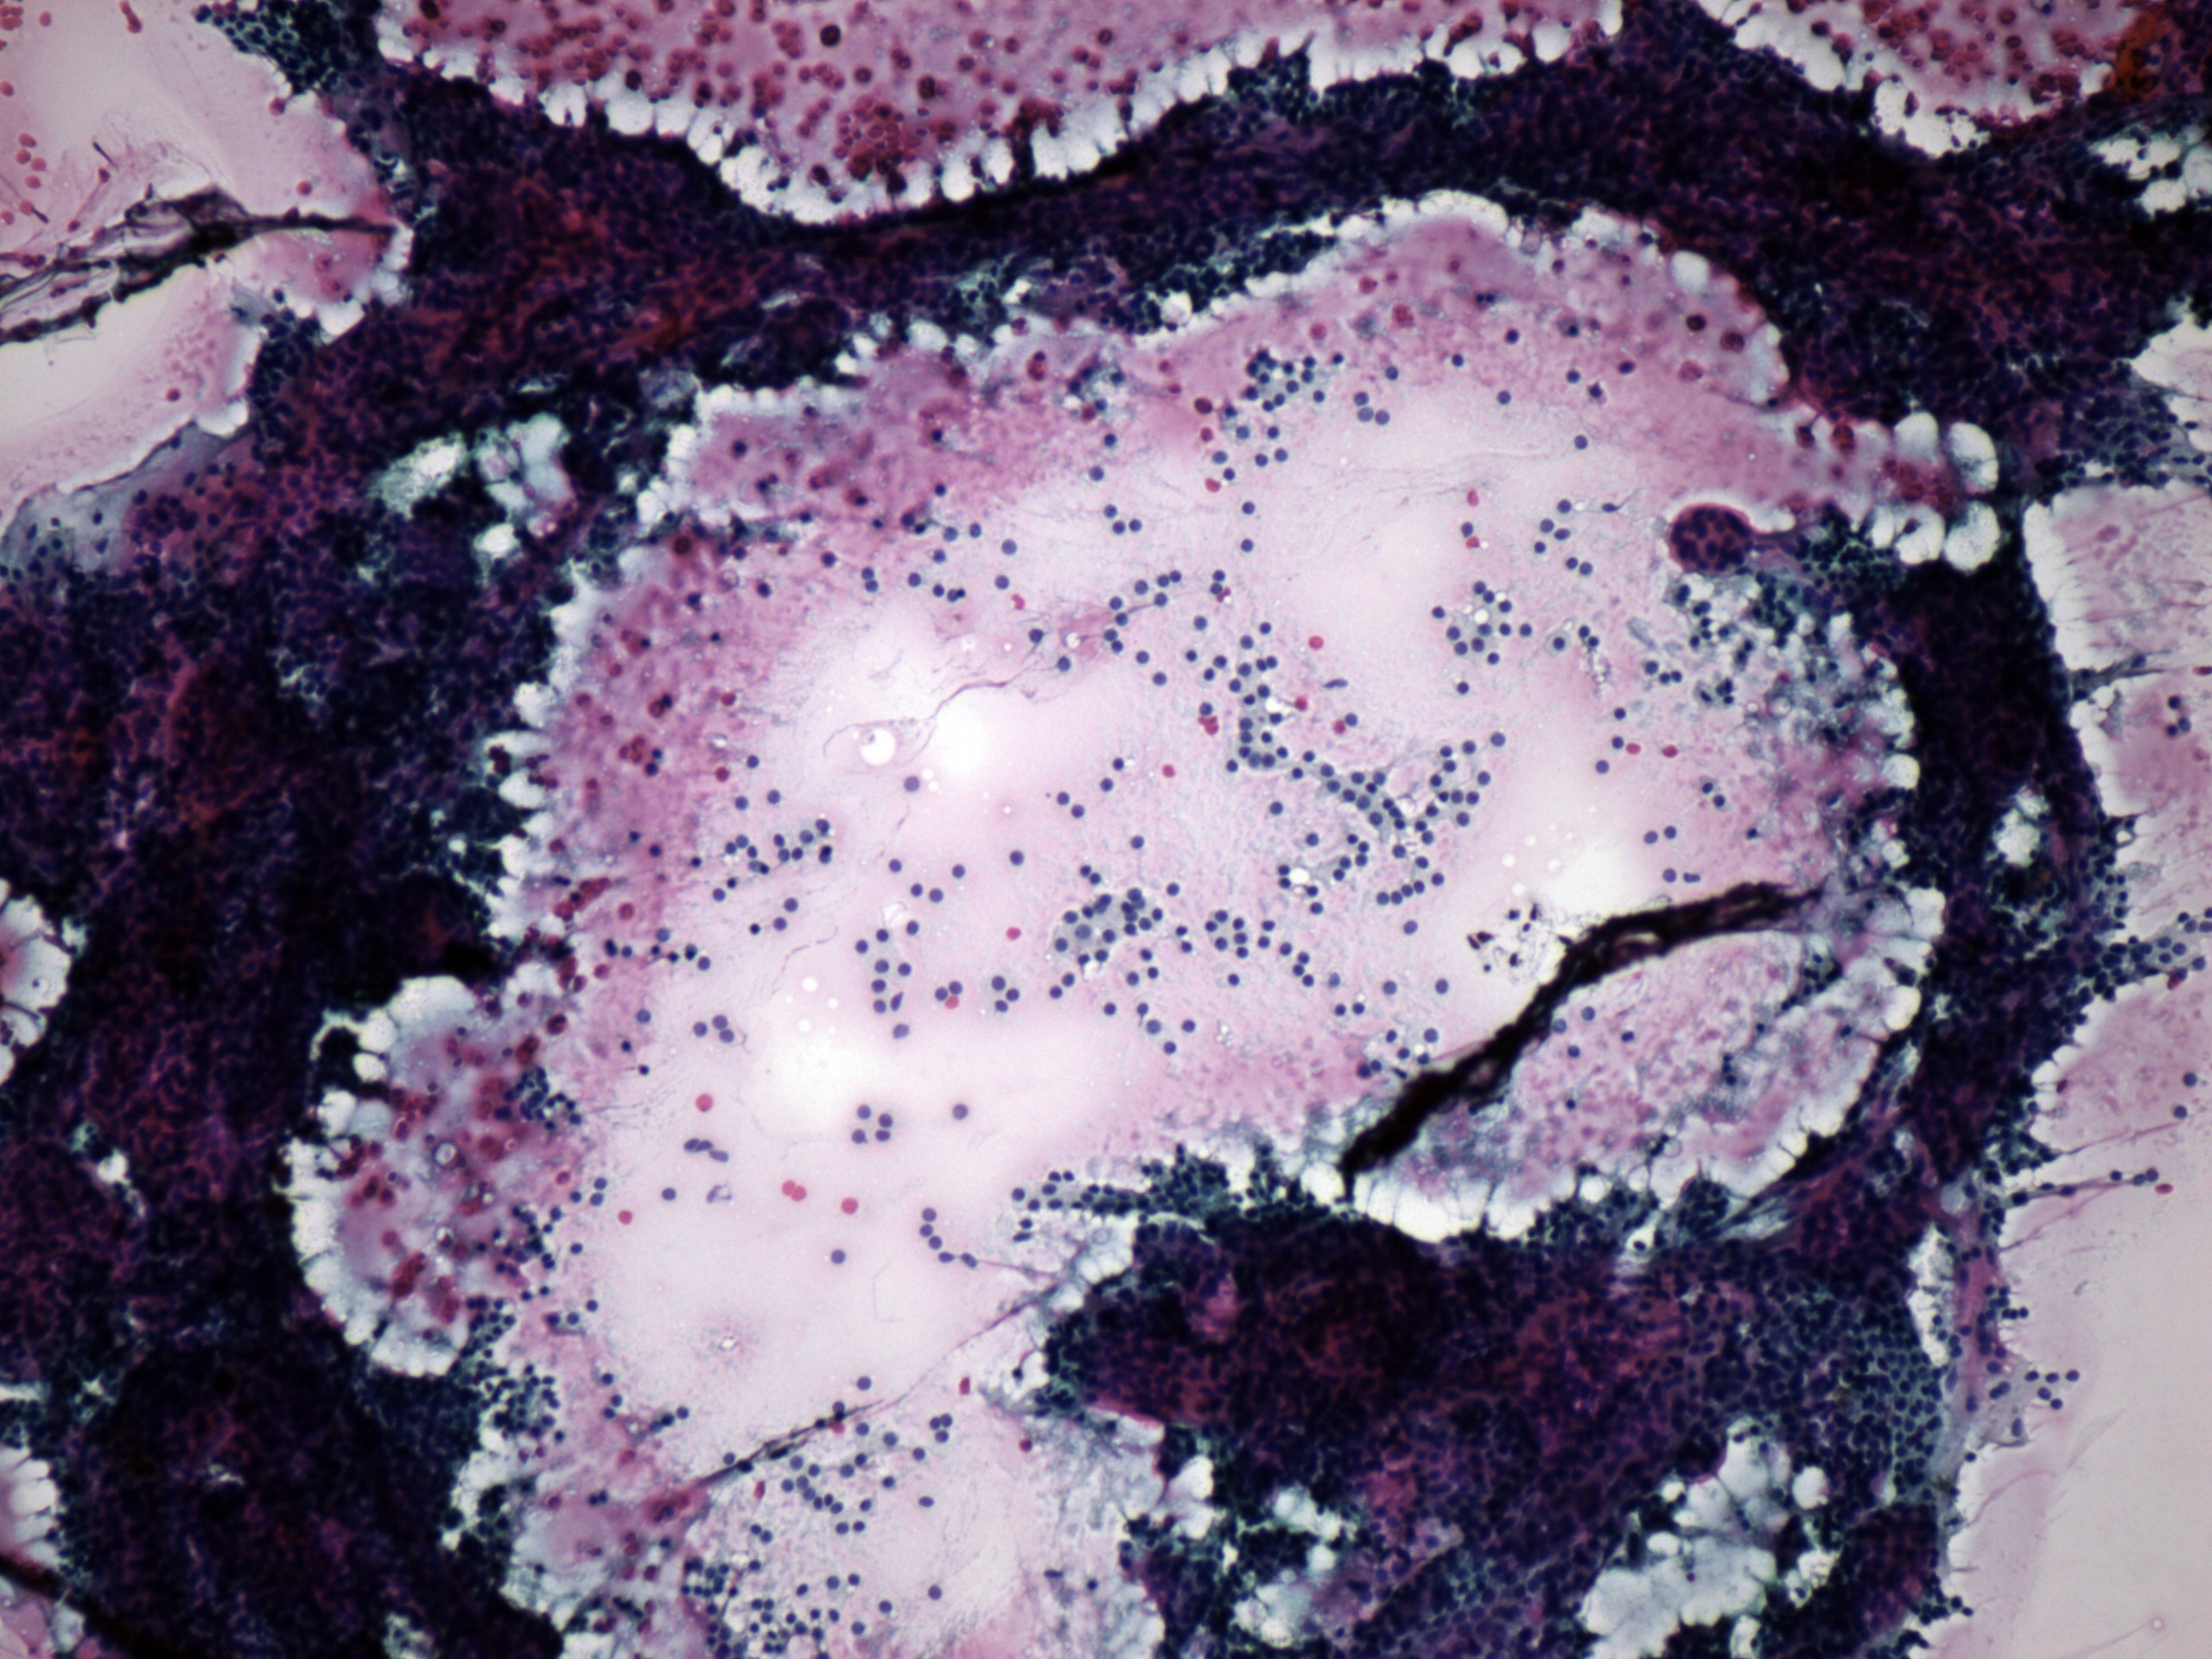

Benign nodular hyperplasia - Case 60. (cytologic picture 1)

Pap-smear, 100x. There is diffuse colloid in the background. Follicular cells are located in a large arborizing hyperplastic papillary fragment, in microfollicules and dispersed.